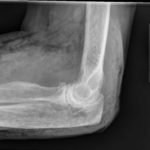

X-Rays of the elbow revealed diffuse striated lucencies throughout the soft tissue, consistent with extensive subcutaneous air throughout the superficial and deep tissues. There was no evidence of a fracture.

The patient discussed here had a LRINEC score of 0. However, the physical exam finding of crepitus, coupled with his history of immunocompromised status and subcutaneous air on X-ray made the diagnosis of NSTI seem likely. However, upon surgical exploration there was no evidence of a NSTI. The most likely mechanism for the subcutaneous air found on this X-ray was that the wound at the elbow acted as a one-way valve for air to enter and collect within the soft tissues. This case is an example of how clinical suspicion and diagnostic scores may not align. Regardless, it is important to keep in mind the clinical picture when deciding to contact consultants. It is recommended, as demonstrated in this case, to obtain a surgical consultation when clinical suspicion is high for a life-threatening diagnosis despite a low risk based on a decision score. It is best to keep in mind that a low LRINEC score does not exclude the diagnosis and that if there is a high suspicion for a NSTI a surgeon should be consulted prior to calculation of a LRINEC score.